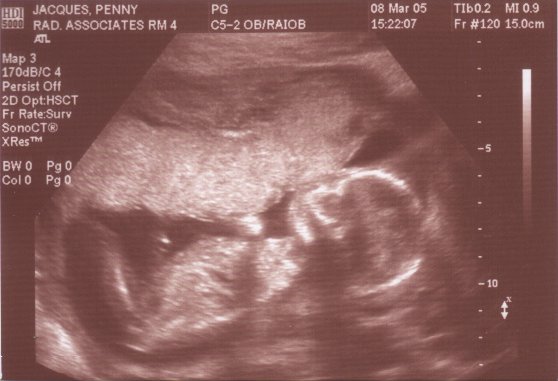

Cong-rrrrrrrrats!!!!

But mine is bigger

Attached Images

parasite2.jpg